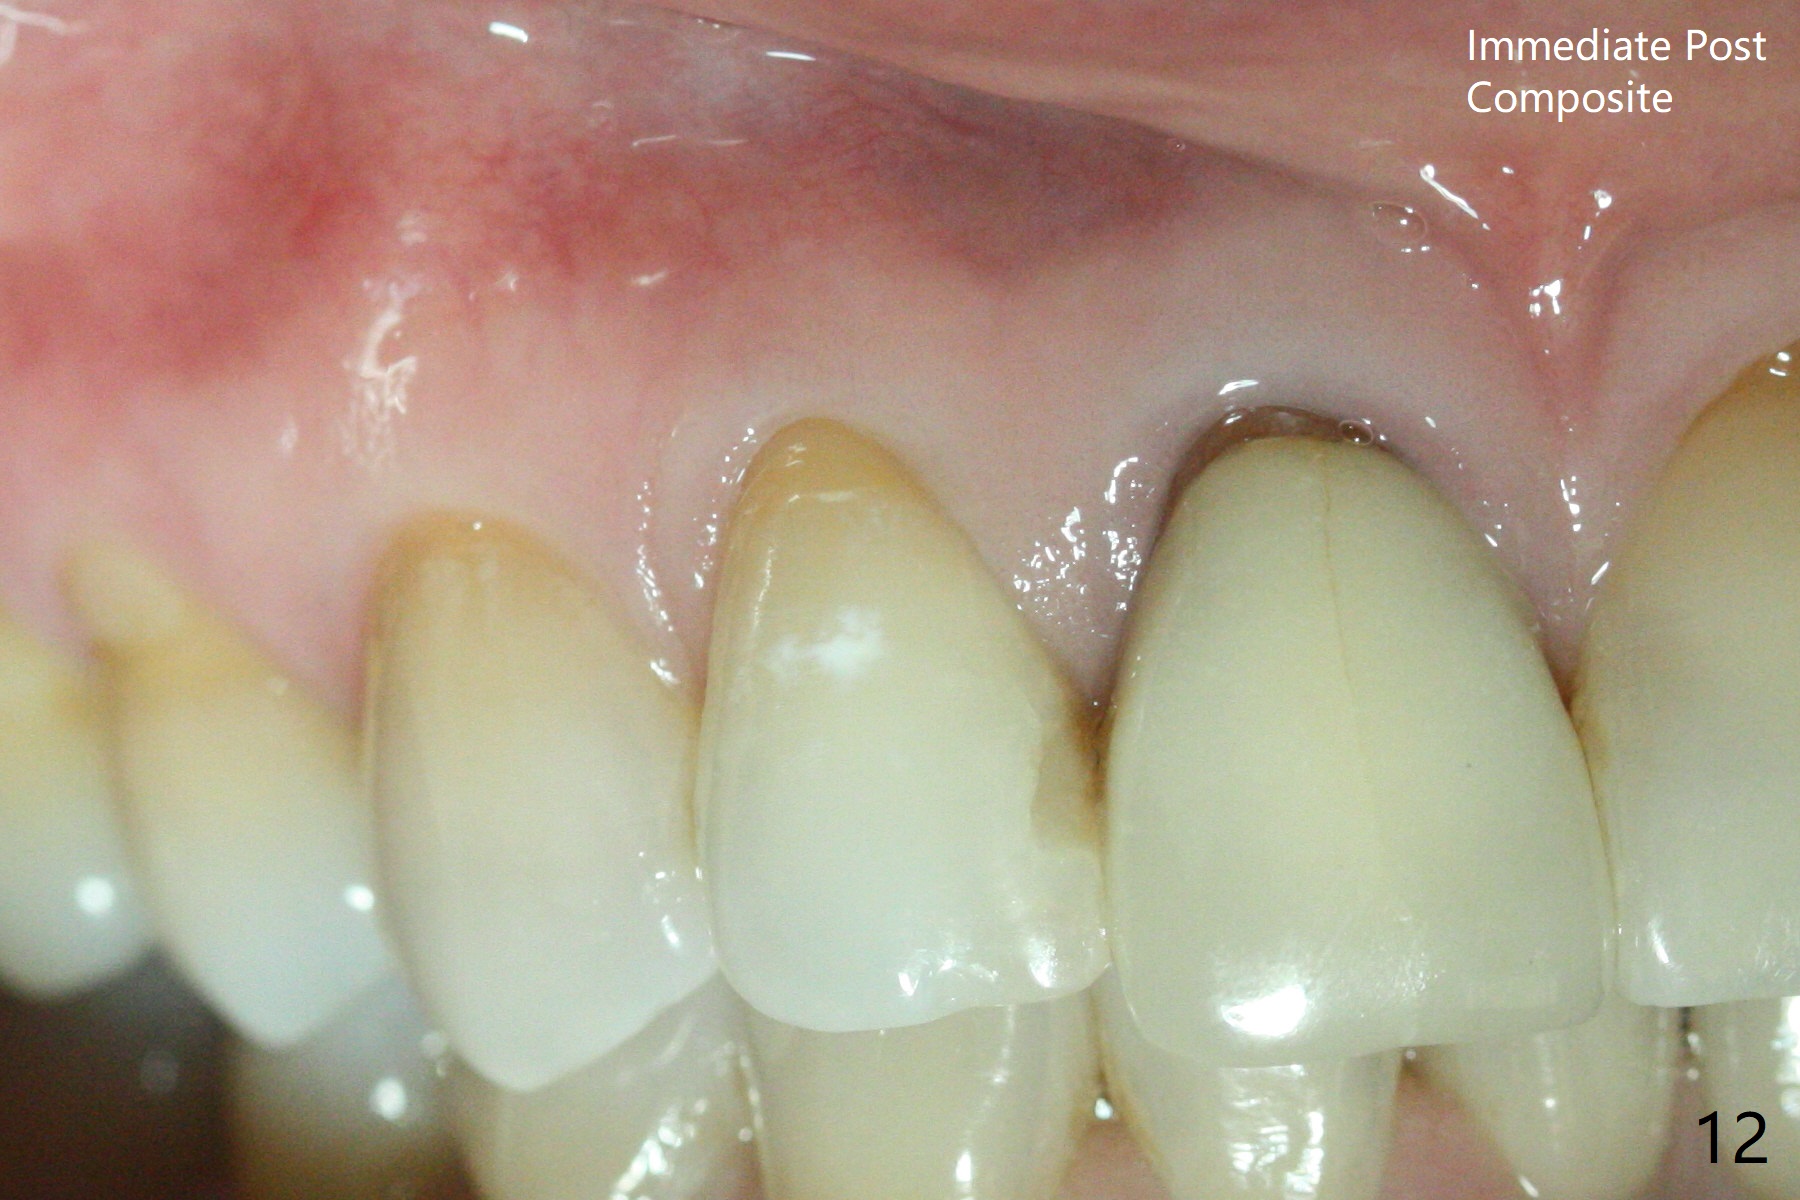

A 46-year-old woman requests a crown for the discolored tooth #7 (Fig.1,2) with mesiolingual composite (Fig.3 C) and periapical radiolucency (*). After RCT (Fig.4,5) with sodium hypochlorite, the tooth #7 is whiter than the ML composite (Fig.6,7). The patient returns 1 day post RCT for in house internal and external bleaching (Fig.8) with 35% hydrogen peroxide gel closed in the canal when she leaves. Three weeks later, the lateral incisor has the shade as the neighboring natural teeth (Fig.9,10). After the lightest shade composite placed in the canal and the access hole (Fig.11), the lateral looks better than the central with a crown and cervical discoloration (Fig.12).